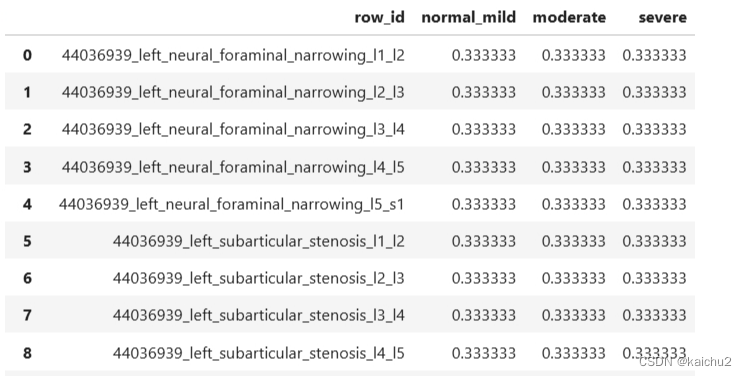

2.4、sample_submission说明

最终需要提交的格式

row_id:行编号,每个编号代表表格中的一行数据。

normal_mild:正常到轻度,这一列显示了从正常到轻度左脑前额叶功能受损的概率值。

moderate:中度,展示了中度左脑前额叶功能受损的概率值。

severe:重度,显示了重度左脑前额叶功能受损的概率值。

比如:44036939_left_neural_foraminal_narrowing_l1_l2这个是由study_id+condition+level组成的,表示在左神经椎间孔狭窄和左神经椎间孔狭窄的不同部位(如L1-L2, L2-L3等)以及左下方关节突狭窄在不同部位(如L1-L2, L2-L3等)情况下,正常到轻度、中度和重度左脑前额叶功能受损的概率值。

通过对所有数据的分析,可以看出来这个是一个图像三分类任务,最后对每个患者的情况进行一个评分。